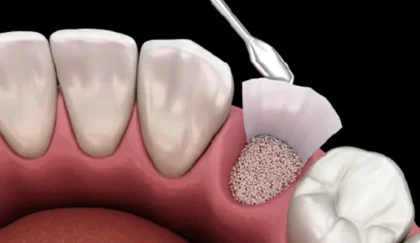

GBR

インプラントを安全・確実に埋入するためには、骨の高さだけでなく幅も十分にあることが重要です。「GBR(Guided Bone Regeneration)」は、骨の幅が不足している場合に行う骨造成法で、人工膜(メンブレン)と補填材を使用して、骨の再生を促します。この治療は、インプラント手術と同時に行う場合もありますが、骨の状態によっては、骨が安定するまで約4ヶ月〜6ヶ月待ってからインプラントを埋入するケースもあります。そのため、通常より治療期間が長くなることがあります。

症例